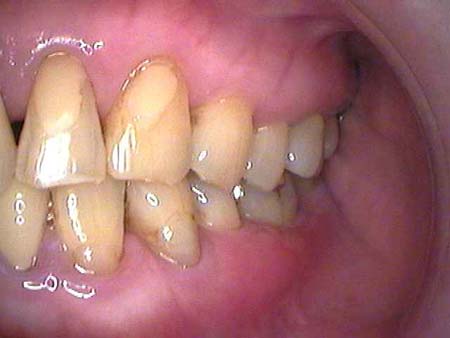

| ○ | そうですよね、わかるから(笑) 私の歯はね、私の歯って黄色いのよね、それが気にいらなくってさ、いくら磨いても白くならないのよ。 ちょっとね、黄色っぽいの。そう言ったら黄色い歯の方が丈夫だってみんなに言われて |

| ● | 日本人は黄色人種ですしね。有色人種ですから少しくらいは…… |

| ○ | でも子供たちはさ、小さい時から磨いていて、それをみていると白いじゃない。だから羨ましくって。ここに来るまで歯石も取らないできたからわからないのよ。 |